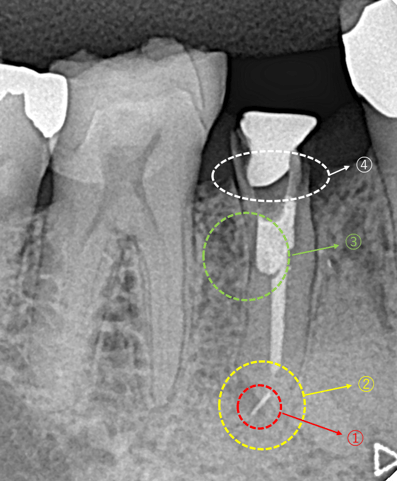

他院で抜歯宣告された歯です。下の奥から3番目の第2小臼歯です。この歯には4つの問題点があります。

①治療用の器具が根の先で折れている(赤点線囲)

②根の先に病巣がある(黄点線囲)

③土台を入れるために歯を削ってありますが、その方向が本来の方向とは異なる方向に削られている。(緑点線囲)

④残っている自分の歯が歯肉の高さスレスレである(白点線囲)